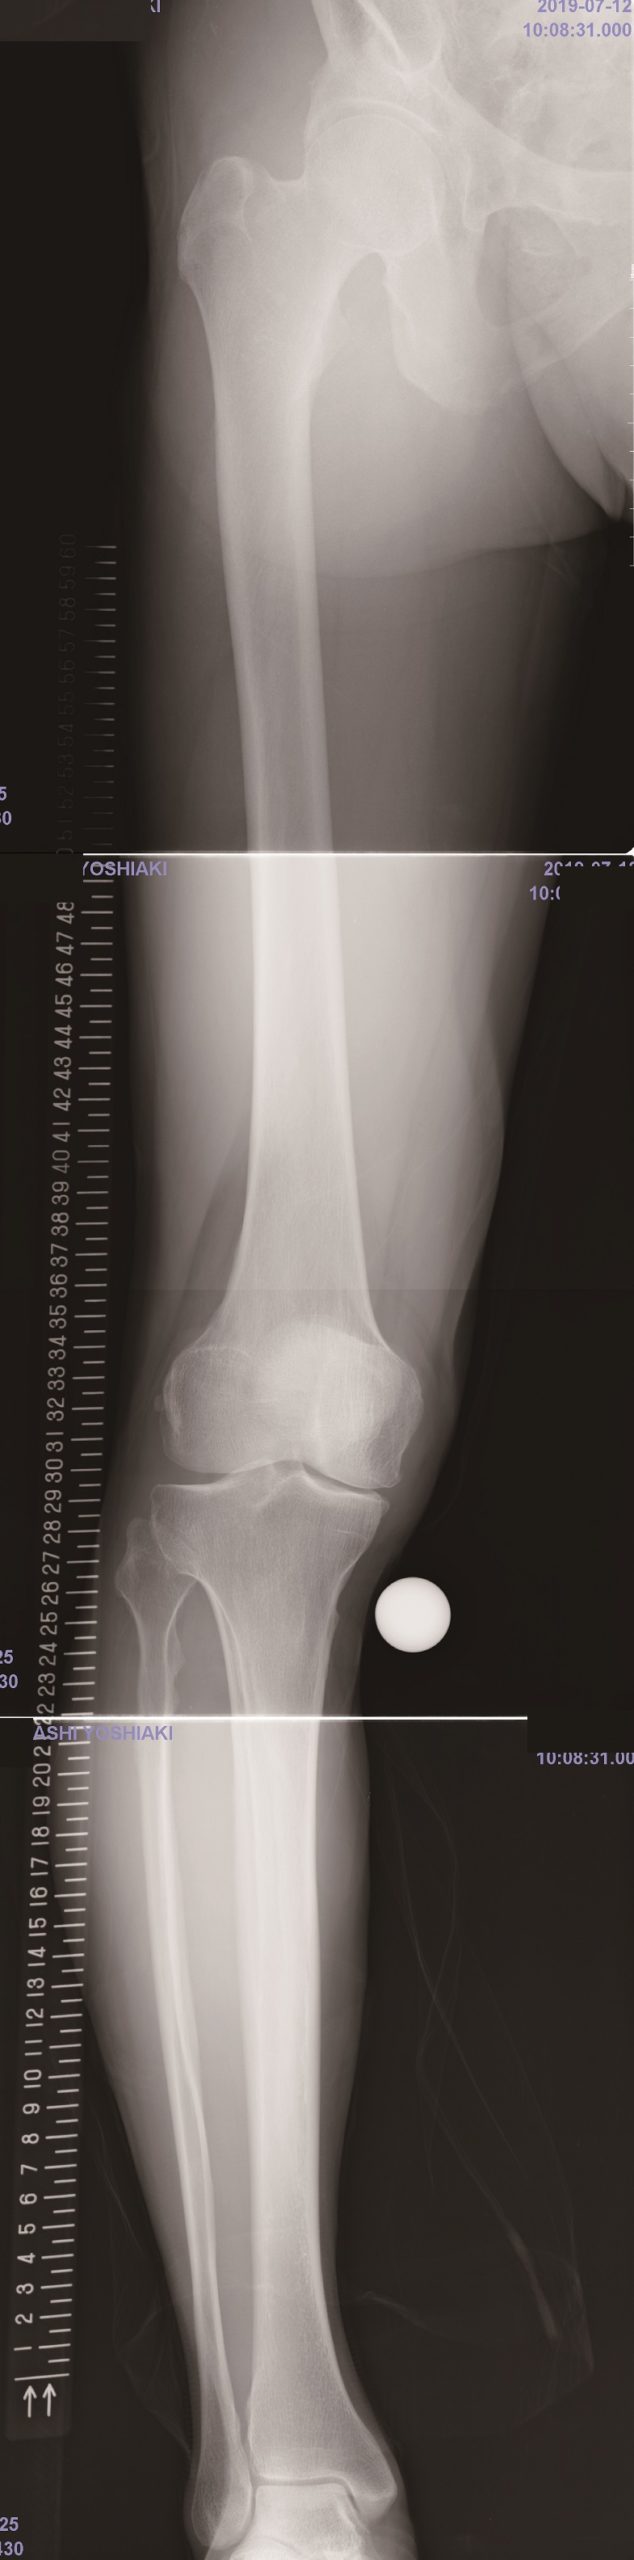

WAKABAYASHI-YOSHIAKI_LL_R_AP

3. Closed wedge 高位脛骨骨切り術

4. WAKABAYASHI-YOSHIAKI_LL_R_AP